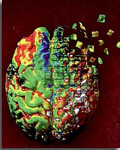

C’est à Prague en république tchèque que s'est tenu le 9th international conference Alzheimer’s and Parkinson‘s Diseases.

C’est à Prague en république tchèque que s'est tenu le 9th international conference Alzheimer’s and Parkinson‘s Diseases.